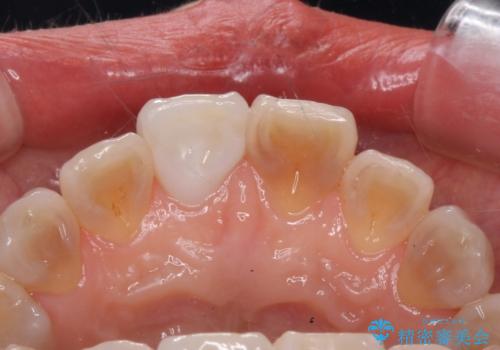

転んで前歯が折れた 色合いの難しい歯のセラミック修復

- 転倒し前歯を地面に強打して折れたとのことで来院。

幸い神経は生きており、セラミックでかぶせることになりました。

テトラサイクリン歯といって縞模様の強い歯の色調再現を行いました。

まず保険治療でコンポジットレジン修復を行い、神経の状態を確認した後、クラウンによる修復を行いました。